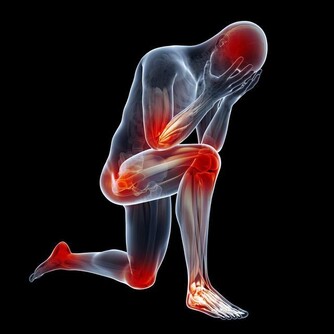

中年人時常覺得腰酸背痛,渾身沒有力氣,而且也懶得動彈,不願意運動,這也說明衰老正慢慢襲來。所以,中年人不要懶惰,而是根據自己的實際情況,進行一些運動,或者做做家務,讓自己活動起來。